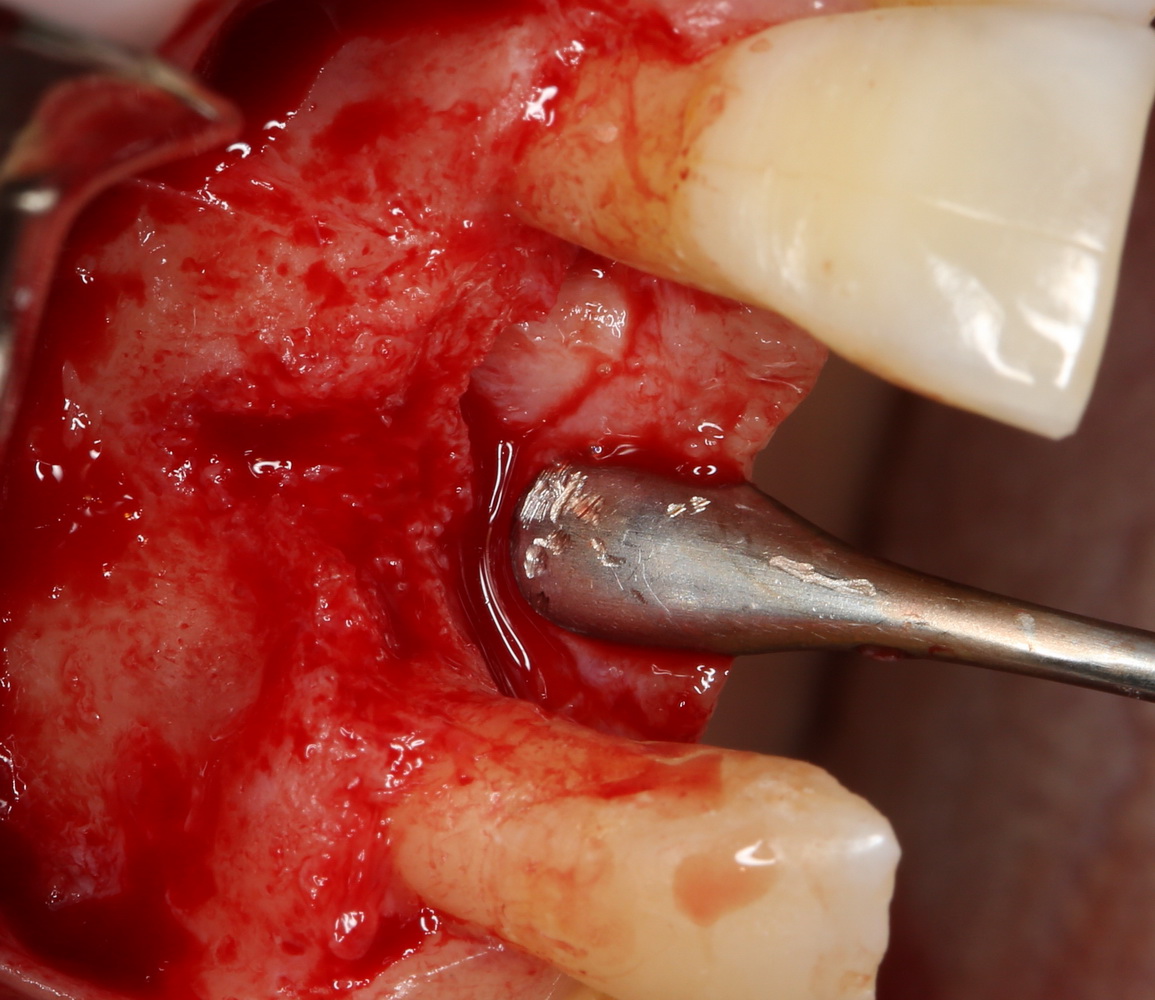

или, непосредственно, со скелетированного участка операционной раны. Можно даже доступ для синуслифтинга сделать с помощью остеохарвестера, а заодно — собрать аутокостную стружку:

Например, в следующей ситуации:

Оставить так, как есть — это значит, сильно рисковать имплантом и объемом альвеолярного гребня — фактически, большая часть импланта пятого зуба «висит в воздухе». Поэтому получившуюся костную полость мы заполняем аутокостной стружкой в смеси с Bioss и закрываем коллагеновой мембраной BioGide: